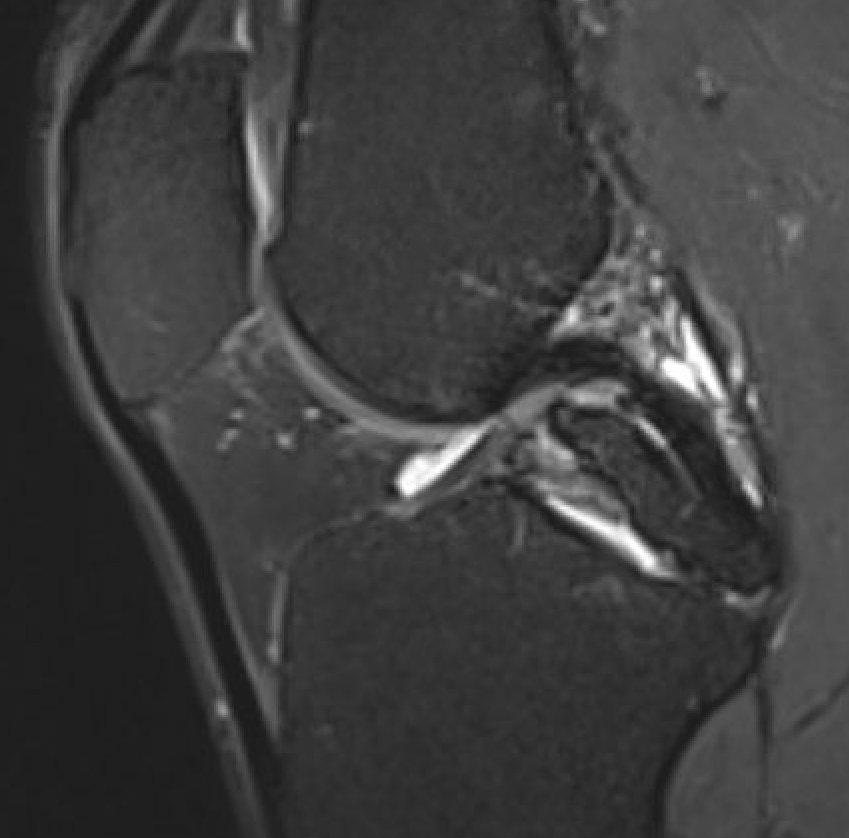

MRI

PCL completely torn

PCL midsubstance tear with lengthening

PCL tibial avulsion

PCL femoral avulsion